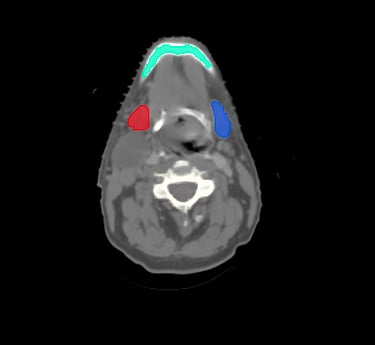

Head & Neck

Choose from a combined structure volume including BrainStem, Brain, Chaism, Mandible, Optic nerves Trachea and many more, or choose individual split sub-levels.